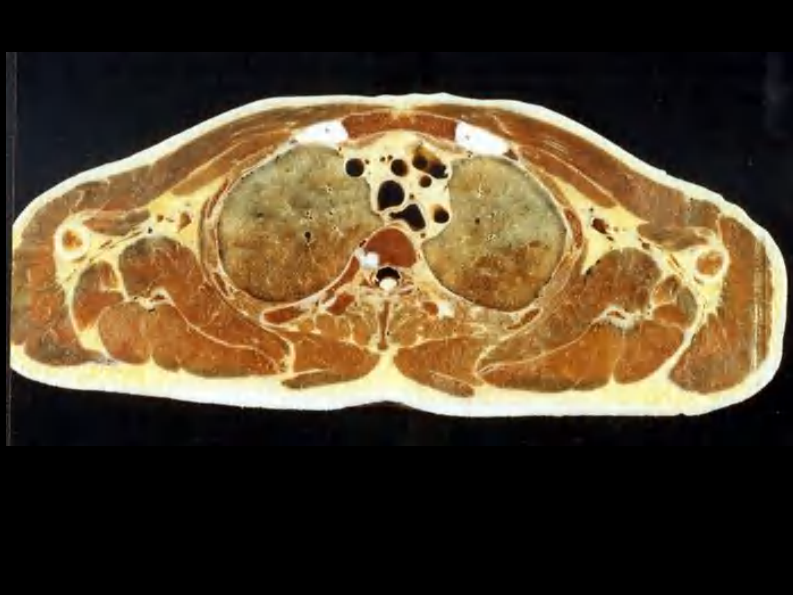

07 纵隔连续横断层解剖及CT.pdf